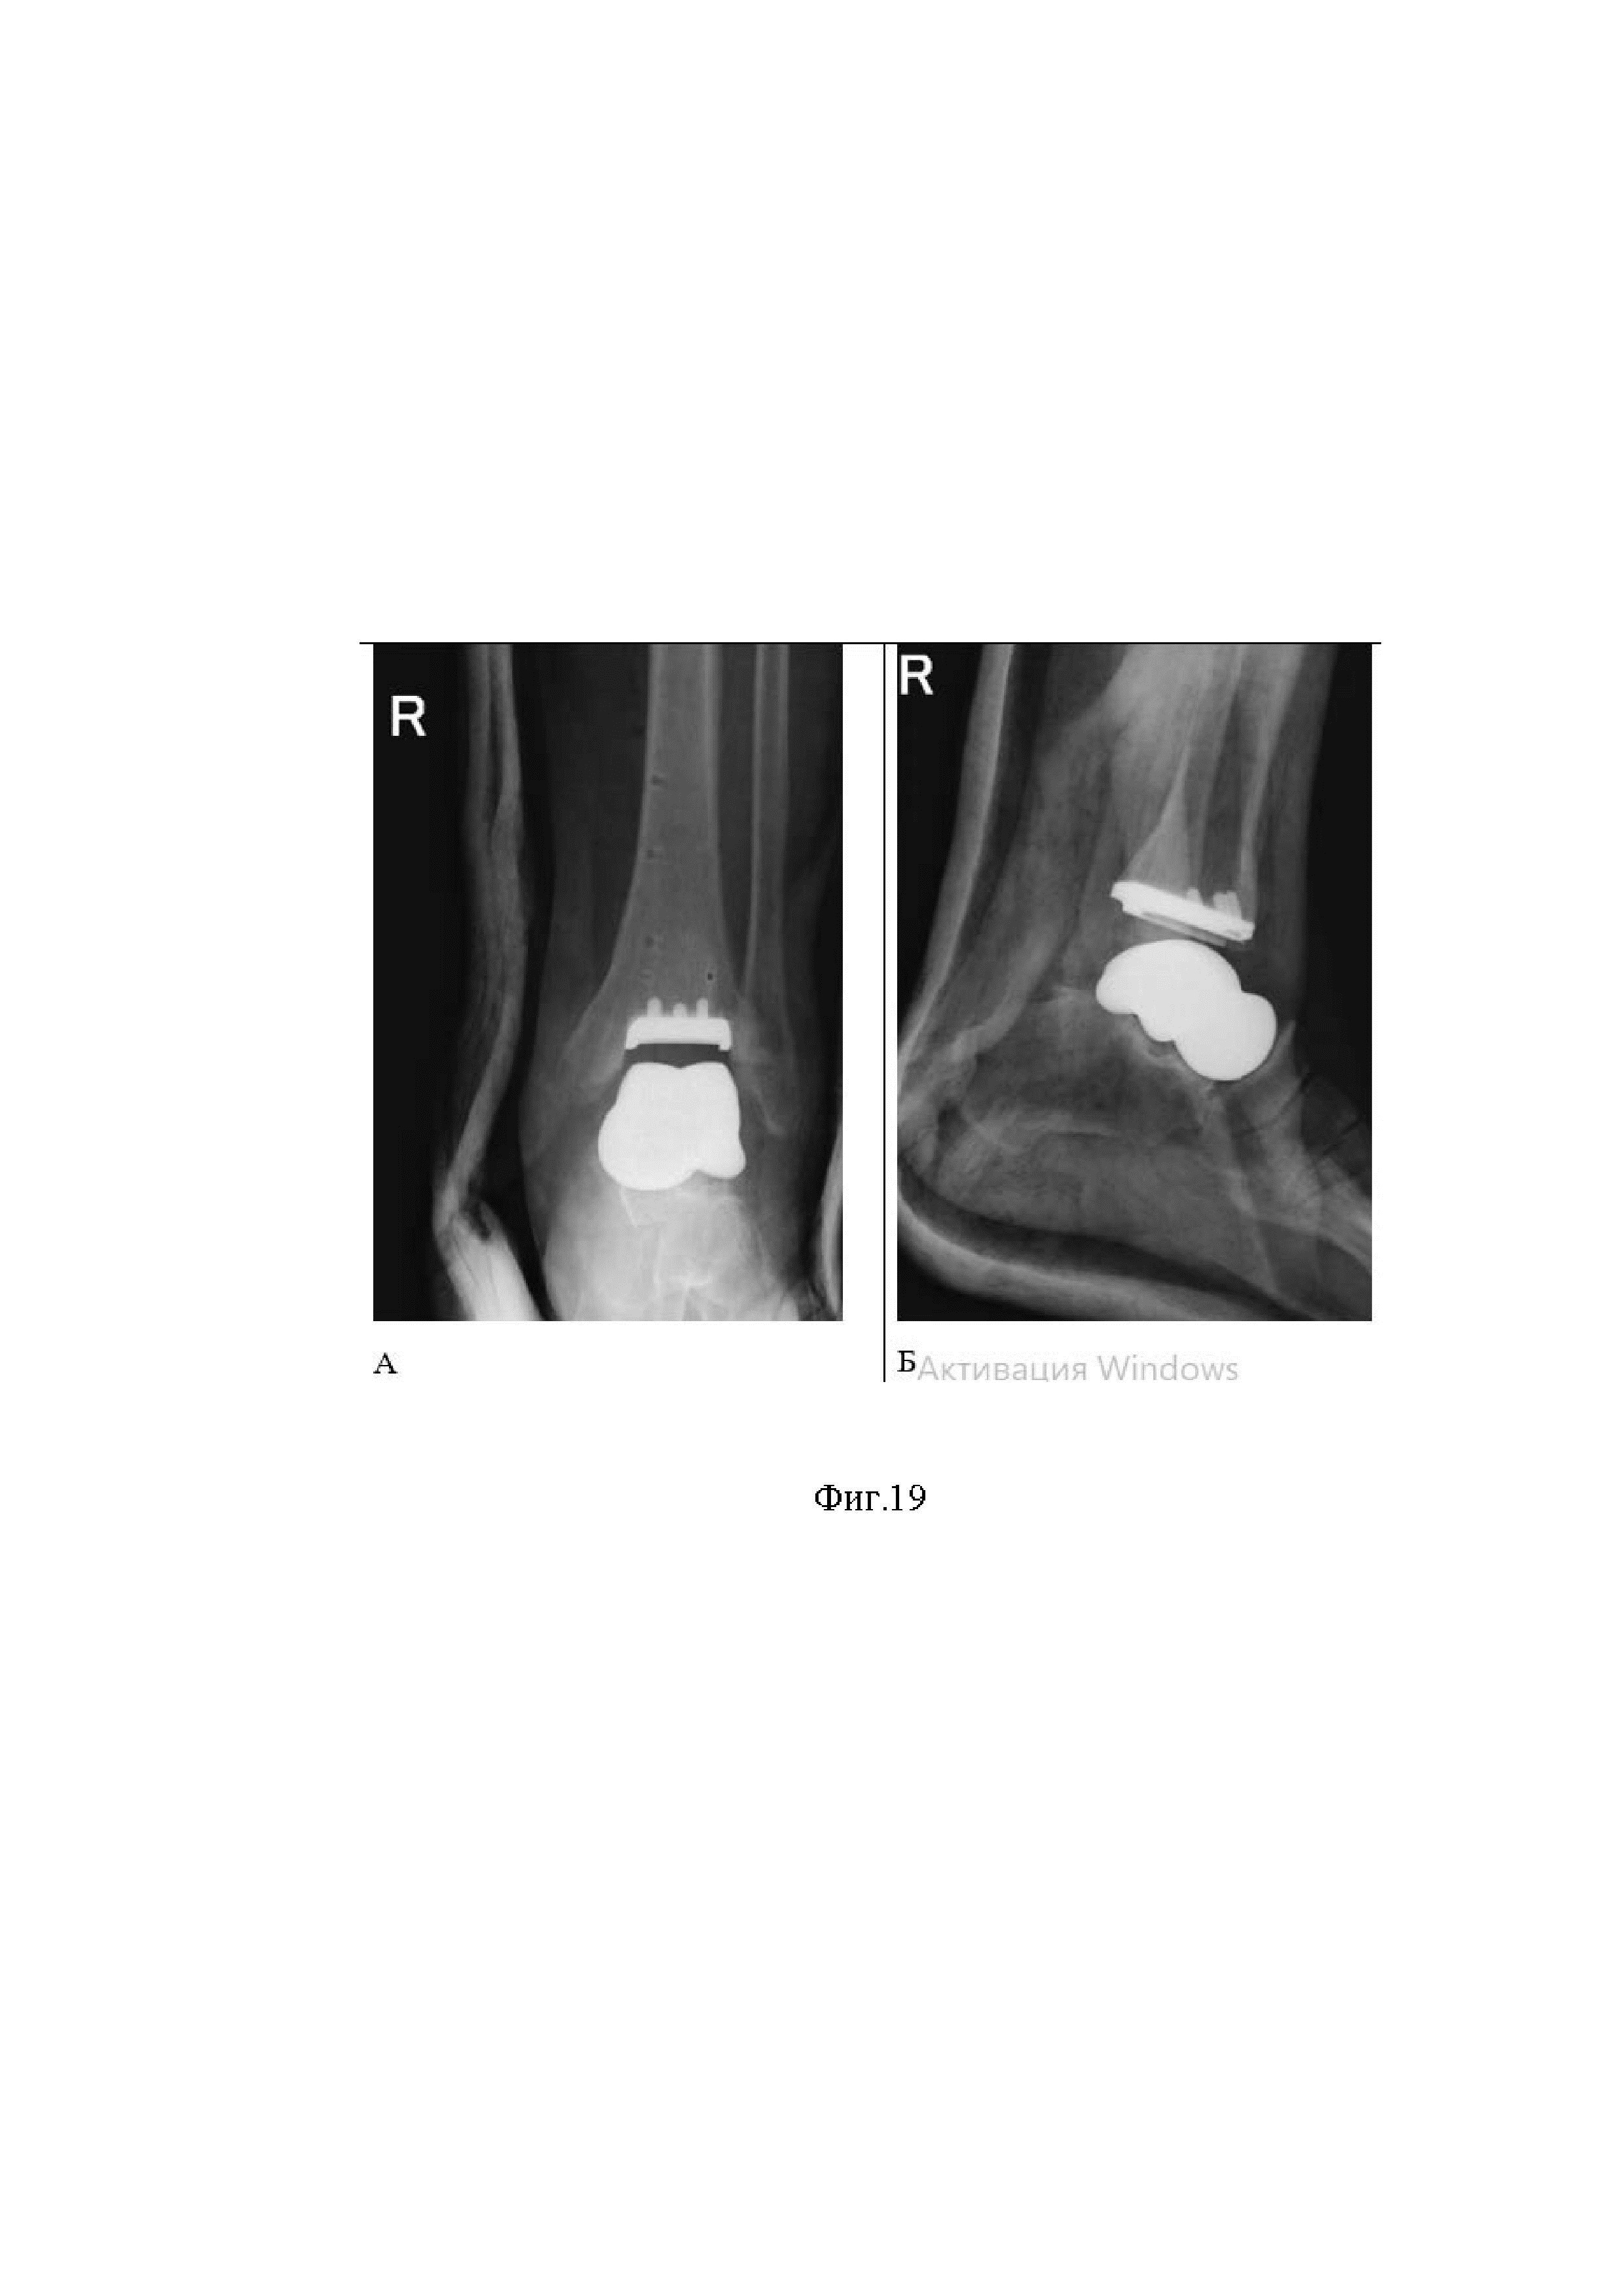

Изобретение относится к медицине, а именно к травматологии и ортопедии, хирургии стопы, и может быть использовано при лечении тотальных и субтотальных дефектах костного вещества таранной кости различного генеза. Изобретение может быть применимо для лечения пациентов с исходом некроза таранной кости различной этиологии, посттравматического остеоартроза голеностопного сустава с формированием эквино-варо-приведенной деформации стопы за счет эндопротезирования голеностопного, таранно-ладьевидного, подтаранного суставов оригинальным эндопротезом таранной кости, воспроизводящим нормальную анатомию таранной кости и конфигурацию сочленяющейся суставных поверхностей таранно-ладьевидного, подтаранного суставов, поверхностей между фиксированным полиэтиленовым вкладышем и тибиальным компонентом эндопротеза голеностопного сустава. Акутальность Посттравматический асептический, аваскулярный, неясного генеза некроз таранной кости является тяжелым инвалидизирующим заболеванием, приводящим к формированию кист таранной кости, варусной или вальгусной деформации стопы, остеоартрозу голеностопного, подтаранного и Шопарова суставов последних стадий, приводящей к быстрой инвалидизации пациентов. Диагностика некроза таранной кости различной этиологии на ранних стадиях затруднена, так как, пациенты обращаются за помощью на поздних стадиях заболевания, когда консервативное лечение неэффективно и сформировалась грубая деформация стопы и голеностопного сустава. На сегодняшний день общепринятым является хирургическое лечение. В исторической ретроспективе основным методом лечения некроза таранной кости различной этиологии считалась астрагалэктомия, рекомендованная в случаях самых тяжелых поражений таранной кости, таких как фрагментация, коллапс, рассасывание, невозможность сохранения суставов, окружающих таранную кость [1]. Функциональные исходы этой операции не соответствуют современному уровню ожиданий пациентов и требований ортопедов к исходам оперативного лечения. В современное время хирургическое лечение пациентов с некрозом таранной кости различной этиологии и его последствиями обычно представлено большеберцово-таранно-пяточным артродезом, который дополняется различными реконструктивными вмешательствами по показаниям. Такой вид хирургического лечения, несмотря на свои достоинства, обладает рядом существенных недостатков, таких как высокая травматичность, необратимая потеря движений в функционально значимых суставах, высокий риск несращений, большая частота остаточных деформаций, необходимость длительных сроков иммобилизации конечности [2,3,4,5]. В последнее десятилетие отмечается повышенный интерес к данной проблематике как в англоязычной, так и в отечественной литературе, что проявляется большим количеством публикаций, клиническими случаями [6,7,8,9,10,11]. При анализе современной литературы, отмечается потребность в переходе от артродеза к более современным, функциональным, щадящим методам лечения. Возникает закономерный вопрос: каким образом преодолеть существующие недостатки и улучшить результаты лечения пациентов с некрозом таранной кости различной этиологии и его последствиями. Потенциальным решением данной проблемы является индивидуальное эндопротезирование таранной кости в комбинации с тибиальным компонентом эндопротеза голеностопного сустава и фиксированного с тибиальным компонентом, полиэтиленовым вкладышем. Ключевые слова: Аваскулярный некроз, асептический некроз, аваскулярный некроз, остеонекроз, артродез, эндопротезирование, голеностопный сустав, таранная кость, индивидальный эндопротез таранной кости, эндопротез голеностопного сустава Причинами формирования посттравматической эквино-варо-приведенной деформации стопы образования частичных и полных дефектов таранной кости являются травмы, опухоли, исход асептического, аваскулярного, различной этиологии некроз таранной кости. В течение многих лет известен способ лечения посттравматической эквино-варо-приведенной деформации стопы с дефектами таранной кости и ее асептическом аваскулярном некрозе посредством операции панталарного артродеза, целью которого является достижение костного сращения между большеберцовой, пяточной, ладьевидной костями и остатками таранной кости [16]. Во всех случаях используют замещение дефекта различными пластическими материалами [17, 18, 19], практически всегда используют различные наружные или внутренние фиксаторы. Способ осуществляется следующим образом: Под СМА после обработки операционного поля рассекают мягкие ткани в проекции латеральной лодыжки от полюса лодыжки на 10-15 см выше по ходу малоберцовой кости. Рассекают кожу, клетчатку. Поднадкостнично выделяют латеральную лодыжку. Производят остеотомию малоберцовой кости на 50 мм выше голеностопного сустава, дистальный фрагмент малоберцовой кости удаляют. Вскрывают голеностопный сустав, скелетируют пяточную, таранную и большеберцовую кости. Производят ревизию голеностопного и подтаранного суставов и удаляют остатки суставного хряща с таранной и большеберцовой костей, а также с подтаранного сустава пяточной кости. С помощью металлического сверла производят множественную перфорация суставных поверхностей прилежащих костей. Выполняют доступ с подошвенной стороны к пяточной кости согласно технологии. В костно-мозговой канал большеберцовой кости через пяточную кость вводят спицу-направитель в правильном положении стопы (с коррекцией деформации пяточной кости и стопы). Ригидными сверлами формируют канал в пяточной и большеберцовой костях. В канал вводят блокируемый стержень. Выполняют последовательное блокирование дистальной части стержня 2 винтами в пяточную кость согласно технологии. Производят установку в проксимальном отделе гвоздя 2 спиц для осуществления дистракции и контракции. Производят контракцию голеностопного сустава согласно технологии до соединения суставных поверхностей. В положении контракции производят блокирование стержня в проксимальном отделе 2 винтами. Производят костную аутопластику суставных щелей костнопластическими материалами. Устанавливают заглушку в дистальный отдел блокируемого стержня. Рану многократно промывают растворами антисептиков. Накладывают послойные швы на раны. Конечность иммобилизуют до коленного сустава на 2-3 месяца с исключением осевой нагрузки. Данный способ имеет ряд недостатков: 1. В случае успеха при достигнутом сращении костей возникает необратимый дефицит объема движений стопой [20, 21]. 2. Высокое количество не сращений с остаточным болевым синдромом [22]. 3. Дегенеративно-дистрофические изменения в смежных суставах [23,24] 4. Усталостные переломы сочленяющихся костей, остаточные деформации стопы [25,26]. Наиболее близким к заявляемому способу лечения посттравматической эквино-варо-приведенной деформации стопы с дефектами таранной кости и ее некрозе различной этиологии, является индивидуальное эндопротезирование таранной кости в сочетании с полиэтиленовым вкладышем и тибиальным компонентом эндопротеза голеностопного сустава. Указанный способ лишен недостатков, перечисленных выше. Первые упоминания об эндопротезирование таранной кости относится к японским авторам [27]. В настоящее время существует большое количество вариантов индивидуальных имплантатов таранной кости из различных материалов [28,29]. Однако, анализ результатов имплантации эндопротеза таранной кости при посттравматических деформациях, и грубых дегенеративно-дистрофических изменениях в голеностопном, суставе указывают на серьезную проблему, а именно: в большинстве случаев тяжелые дегенеративные изменения, последствия поражения пилона большеберцовой кости делают невозможным первичную имплантацию современных эндопротезов голеностопного сустава и изолированной замены таранной кости ее индивидуальным эндопротезом, существующих на рынке медицинских изделий в травматологии и ортопедии, причинами служат неправильная опоры блока таранной кости на пилон большеберцовой кости с исходом в прогрессирование грубых деформаций и сохранению выраженного болевого синдрома [30,31]. Таким образом, возникла необходимость предложить способ, чтобы предотвратить деформацию, болевой синдром и сохранить движения в голеностопном, подтаранном и таранно-ладьевидном суставах. Методом выбора для решения обозначенной проблемы в доступной литературе не нашли. Технический результат предлагаемого изобретения заключается в коррекции деформации, устранении болевого синдрома и сохранении движения в голеностопном, подтаранном и таранно-ладьевидном суставах за счет использования индивидуального импланта таранной кости в сочетание с тибиальным компонентом и фиксированным в него полиэтиленовым вкладышем эндопротеза голеностопного сустава. Для решения заяленного технического результата предлагается способ эндопротезирования голеностопного сустава при посттравматической эквино-варо-приведенной деформации стопы и голеностопного сустава, при некрозе таранной кости различной этиологии с посттравматическим остеоартрозом голеностопного сустава включающий предоперационное планирование, наложение турникета, осуществление оперативного доступа по передней поверхности голеностопного , в пространстве между сухожилиями длинного разгибателя 1 пальца и передней большеберцовой мышцы послойно рассекаются кожа, подкожно-жировая клетчатка до кости, защищая сосудисто - нервный пучок, выполнение субпериостальной диссекции в латеральном и медиальном направлении с обнажением пилона большеберцовой кости, шейки и головки таранной кости, голеностопного сустава и проведение эндопротезированияю. Отличием является то, что на стадии предоперационного планирования проводят МСКТ-исследование «здоровой» противоположной таранной кости и проводят ее зеркальную реконструкцию, оценивают основные размеры реконструированной таранной кости и адаптируют ее используя виртуальные 3D возможности к пострадавшей стороне, создают индивидуальный имплантат таранной кости с учетом таких показатели как: форма, размеры, объем не поврежденной контралатеральной таранной кости отзеркаленной и адаптированной к стороне планируемой имплантации, на блоке индивидуального имплантата таранной кости формируют вырезку по типу «ласточкиного хвоста», точно подходящую по формам и размерам к полиэтиленовому вкладышу эндопротеза голеностопного сустава, на виртуальном предоперационном планировании оценивают результаты измерений, взаимоотношений и пространственной ориентации таранной кости в подтаранном, таранно-ладьевидном, голеностопном суставах, с оценкой таких показатели как: тало-метатарзальный угол, ось таранной кости, таранно-пяточный угол (угол Кита), на стадии операционного вмешательства проводят иссечение синовиальной оболочки голеностопного сустава, резецируют остатки таранной кости и удаляют их, производят астрагалэктомию таранной кости, в сформированное ложе устанавливают индивидуальный эндопротез таранной кости точно адаптированный по форме и размеру к полиэтиленовому вкладышу и тибиальному компоненту эндопротеза голеностопного сустава, тибиальный компонент голеностопного сустава устанавливают на костный цемент, в тибиальный компонент устанавливают импактор для впрессовывания вкладыша, устанавливают полиэтиленовый вкладыш, затем турникет снимают, выполняют гемостаз, рану послойно ушивают, накладывают асептическую повязку, выполняют гипсовую иммобилизацию глубокой задней гипсовой шиной. Предлагается способ эндопротезирования голеностопного сустава при посттравматической эквино-варо-приведенной деформации стопы и голеностопного сустава при некрозе таранной кости различной этиологии с посттравматическим остеоартрозом голеностопного сустава включающий предоперационное планирование, 3D моделирование будущего индивидуального имплантата таранной кости, моделирование суставных поверхности импланатат таранной кости, адаптирование поверхности таранной кости к полиэтиленовому вкладышу эндопротеза голеностопного сутсава, наложение турникета, осуществление оперативного доступа по передней поверхности голеностопного сустава посередине над голеностопным суставом, выполнение субпериостальной диссекции в латеральном и медиальном направлении с обнажением пилона большеберцовой кости и шейки, головки таранной кости и голеностопного сустава, тотального индивидуального эндопротезирования таранной кости, установки тибиального компонента и фиксированного полиэтиленового вкладыша эндопротеза голеностопного сустава. Отличием является то, что на стадии на стадии предоперационного планирования проводят МСКТ-исследование «здоровой» противоположной таранной кости и проводят ее зеркальную реконструкцию, оценивают основные размеры реконструированной таранной кости и адаптируют ее используя виртуальные 3D возможности к пострадавшей стороне, создают индивидуальный имплантат таранной кости с учетом таких показатели как: форма, размеры, объем не поврежденной контралатеральной таранной кости отзеркаленной и адаптированной к стороне планируемой имплантации, на блоке индивидуального имплантата таранной кости формируют вырезку по типу «ласточкиного хвоста», точно подходящую по формам и размерам к полиэтиленовому вкладышу эндопротеза голеностопного сустава, на виртуальном предоперационном планировании оцениваются результаты измерений, взаимоотношений и пространственной ориентации таранной кости в подтаранном, транно-ладьевидном, голеностопном суставах, с оценкой таких показатели как: тало-метатарзальный угол, ось таранной кости, таранно-пяточный угол (угол Кита), на стадии операционного вмешательства проводят иссечение синовиальной оболочки голеностопного сустава, резецируют остатки таранной кости и удаляют их, производят астрагалэктомию таранной кости, в сформированное ложе устанавливают индивидуальный эндопротез таранной кости точно адаптированную по форме и размеру к полиэтиленовому вкладышу и тибиальному компоненту эндопротеза голеностопного сустава, тибиальный компонент голеностопного сустава устанавливается на костный цемент, в тибиальный компонент установливается импактор для впресовывания вкладыша, устанавливается полиэтиленовый вкладыша. Турникет снимается, выполняется гемостаз, рана послойно ушивается, накладывается асептическая повязка, выполняется гипсовая иммобилизация глубокой задней гипсовой шиной. Используемые термины «зеркальная реконструкция», «отзеркаленая» означают точно подобные и сходный с отражением здоровой части таранной кости, создается ее точная противоположная копия зеркального ее отражения. Сущность изобретения, диагностические матераилы показаны на фиг.1, где показана рентгенография правого голеностопного сустава пациента в прямой (А) и боковой (Б) проекциях (2014 год) отмечается перелом шейки таранной кости правой стопы с вывихом таранной кости в подтаранном, таранно-ладьевидном и голеностопном суставах, тип IV по классификации Hawkins, на фиг.2 рентгенография правого голеностопного сустава пациента в прямой (А) и боковой (Б) (2014 год) отмечается вправленный переломовывих таранной кости, внутренняя фиксация винтами, фиг.3 (А) показана фотография обеих стоп пациента вид сверху, Б -правая стопа вид сбоку отмечается приведение и супинация правой стопы с вершиной деформации на уровне таранно-ладьевидного сустава, фиг.4. (А) показана фотография левой стопы, Б - фотография правой стопы показывающая формированием эквинусной установки правой стопы на уровне голеностопного сустава, в сравнении с левой стопой, появление «высокого» свода правой стопы на фоне приведения и супинации правой стопы, фиг. 5 - фотография обеих стоп вид сзади, отмечается варусная установка пяточной кости правой стопы, фиг. 6 рентгенография обеих стоп пациента в опоре прямая проекция. Отмечается приведение среднего и переднего отдела правой стопы на уровне таранно-ладьевидного сустава, фиг.7 рентгенография правого голеностопного сустава пациента в прямой (А) и боковой (Б) проекциях стоя, отмечается исход посттравматического асептического/аваскулярного некроза таранной кости, посттравматическая варусная деформация правой таранной кости, коллапс таранной кости, инородное тело (фрагменты винтов в теле правой таранной кости), посттравматический правосторонний крузартроз 3 ст, фиг.8 показана МСКТ правого голеностопного сустава пациента. Правосторонний крузартроз 3 ст. Правый голеностопный сустав деформирован. Суставные поверхности нечеткие, неровные, субхондральный остеосклероз суставных поверхностей с кистовидной перестройкой. Суставная щель нитевидно сужена. Исход посттравматического асептического/аваскулярного некроза правой таранной кости. Фиг.9 показана реконструкцией правого голеностопного сустава и стопы, фиг.10 - 3D моделированием правой и левой стопы, фиг.11 показана техника выполнения МСКТ исследования голеностопных суставов и стопы с имитацией опоры, фиг.12 Тало-метатарзальный угол Б - Схема определения оси таранной кости, фиг.13 Таранно-пяточный угол (угол Кита) А – схема оценки угла Кита на прямой рентгенограмме Б - схема оценки угла Кита на боковой рентгенограмме, фиг.14 предложена компьютерная модель имплантата таранной кости с поверхностью адаптированной к полиэтиленовому вкладышу эндопротеза голеностопного сустава Б – компьютерная модель стопы показывающая взаимоотношения имплантата таранной кости в таранно-ладьевидном и подтаранном суставах, фиг.15 компьютерная модель стопы и голеностопного сустава с установленным индивидуальным эндопротезом таранной кости адаптированного к полиэтиленовому вкладышу и тибиальному компоненту эндопротеза голеностопного сустава А – Вид спереди Б – вид сбоку, фиг.16 Внешний вид индивидуального имплантата таранной кости из материала TI64ELI, фиг.17 Фото голеностопного сустава, посттравматические, дегенеративно-дистрофические изменения таранной и большеберцовой костей, фиг.18 фото операционной раны, имплантированный индивидуальный эндопротез таранной кости Б - Фото операционной раны, имплантированный индивидуальный эндопротез таранной кости в сочетании с фиксированным вкладышем и тибиальным компонентом эндопротеза голеностопного сустава, протез в сборе, фиг.19 показаны послеоперационные контрольные рентгенограммы голеностопного сустава в прямой (А), боковой проекциях (Б). Отмечается имплантированный индивидуальный эндопротез таранной кости в сочетании с фиксированным вкладышем и тибиальным компонентом эндопротеза голеностопного сустава, достигнутая коррекция, положение имплантов удовлетворительное, хороший результат. На фиг. 1,2,3,4,5,6,7,8,9,10,11,12,13,14,15 показаны результаты дооперационного обследования пациента. Решение было достигнуто за счет придания блоку индивидуально изготовленной таранной кости формы стандартных производимых таранных компонентов эндопротеза голеностопного сустава. Как указано выше, при создание имплантата таранной кости учитывались такие показатели как: форма, размеры, объем не поврежденной таранной кости, результаты измерений, взаимоотношений и пространственной ориентации таранной кости в подтаранном, таранно-ладьевидном, голеностопном суставах, оценивались такие показатели как: тало-метатарзальный угол, ось таранной кости, таранно-пяточный угол (угол Кита). Технический результат изобретения достигается тем, что на предоперационном планирование формируют эндопротез таранной кости близкий к нормальной анатомии таранной кости (высота, объем, ширина, длина, суставные поверхности и др.), учитываются пространственная ориентации таранной кости в стопе, на виртуальной модели корригируются сопутствующие деформации таранной кости с учетом измерений таких как: тало-метатарзальный угол, ось таранной кости, таранно-пяточный угол (угол Кита), высота, форма, объем таранной кости, форма суставных фасеток относящихся к таранно-ладьевидному, подтаранному суставам, и размерам к будущему полиэтиленовому вкладышу фиксированному к тибиальному компоненту эндопротеза голеностопного сустава, таким образом, на основе дооперационной оценки изготовлен индивидуальный имплантат таранной кости, на блоке индивидуального имплантата таранной кости сформирована вырезка по типу «ласточкиного хвоста», точно подходящую по формам и размерам к полиэтиленовому вкладышу эндопротеза голеностопного сустава. Совместно с инженером, создана компьютерная модель стопы и голеностопного сустава с установленным индивидуальным эндопротезом таранной кости адаптированного к полиэтиленовому вкладышу (эндопротез таранной кости имеет выемку по параметрам полиэтиленового вкладыша) и тибиальному компоненту эндопротеза голеностопного сустава, соответствующих размеров (фиг.15). После согласования модели, по технологии DMLS, был изготовлен окончательный индивидуальный имплантат таранной кости из материала TI64ELI (фиг.16). За счет совпадения по параметрам сочленения эндопротеза таранной кости и полиэтиленового вкладыша обеспечивается легкая подвижность сустава, значительно снижается, и со временем исчезает болевой синдром. На стадии операционного вмешательства по передней поверхности голеностопного сустава в пространстве между сухожилиями длинного разгибателя 1 пальца и передней большеберцовой мышцы послойно рассекают кожу, подкожно-жировую клетчатку до кости, защищая сосудисто - нервный пучок. Производят субпериостальную диссекцию в латеральном и медиальном направлениях с обнажением пилона большеберцовой кости и шейки и головки таранной кости. Вскрывают голеностопный сустав, синовиальная оболочка которого гипертрофирована, синюшного цвета, полость сустава заполнена прозрачной синовиальной жидкостью (описание пациентов с соответствующим диагнозом). Во время операции удаляют остатки пораженной таранной кости, чем формируют пространство для имплантации индивидуально изготовленной таранной кости (фиг. 17). В сформированное пространство имплантируют индивидуальный эндопротез таранной кости (фиг.18 А), В медиальную суставную щель голеностопного сустава перпендикулярно оси большеберцовой кости устанавливают вилку срединного желоба. К ней присоединяют выравнивающую рамку, через которую бикортикально проводят пин 3,2мм ориентируясь на гребень большеберцовой кости. К пину присоединяют выравнивающую раму в сборе. С помощью выравнивающего крыла с ориентацией на положения гансайтов производят выравнивание: во фронтальной (варусный/вальгусный угол) и сагиттальной плоскости (сгибание, разгибание). В два центральных отверстия направляющей рамы через 2 проводника проводят 2 бикортикальных пина, к которым после удаления рамы присоединяют блок регулировки калибрующей направляющей резекции. Устанавливают блок калибровки фронтальной и сагиттальной резекции, производят выравнивание во фронтальной и сагиттальной плоскостях - определяют размер тибиального компонента 4 лонг. В 4 отверстия регулировочного блока устанавливают 4 спицы Штеймана (2,4 мм), с помощью тибиального углового сверла производят сверление углов большеберцовой кости. Калибрующий блок затем удаляют, устанавливают направляющую резекцию соответствующего размера, производят резекцию согласно опилочному шаблону. После чего калибрующий блок удаляют. Удаляют резецированные фрагменты большеберцовой кости. Устанавливают пробный тибильный компонент, фиксируют 2 спицами Штеймана. С помощью Иглы для заднего и переднего отверстия тибиального компонента формируют отверстия в большеберцовой кости. Пробная имплантация тибиального компонента соответствующего предоперационному и интраоперационному планированию в сборе с индивидуальным имплантатом таранной кости, после чего устанавливают тибиальный компонент и фиксированный в него полиэтиленовый вкладыш на постоянной основе (фиг. 18 Б). После оперативного вмешательства выполняют рентген и МСКТ контроль оперированного голеностопного сустава после операции (фиг. 19). В результате точного соответствия блока таранной кости к суставным поверхностям таранно-ладьевидного, подтаранного суставов, фиксированному полиэтиленовому вкладышу тибиального компонента эндопротеза голеностопного сустава, создается опорность эндопротеза, корригируется сопутствующая эквино-варо-приведенна деформации стопы, обеспечивается опорность ноги, сохраняются движения в голеностопном, подтаранном, таранно-ладьевидном суставах. Способ эндопротезирования голеностопного сустава при посттравматической эквино-варо-приведенной деформации стопы и голеностопного сустава при некрозе таранной кости различной этиологии с посттравматическим остеоартрозом голеностопного сустава обеспечивает образование подвижного, стабильного, биомеханически обоснованного сочленения между большеберцово-таранным, таранно-ладьевидным и подтаранным суставами, что способствует, коррекции деформации, улучшению результатов лечения, сокращению срока лечения, быстрой реабилитации, восстановлению опороспособности конечности, сохранения биомеханики в голеностопном суставе при наиболее тяжелых поражениях таранной кости различного генеза. Пример клинического применения. Пациентка Щ., 1992 года рождения в 2022 году поступила в Городскую клиническую больницу имени С.С. Юдина департамента здравоохранения города Москвы, 4 травматолого-ортопедическое отделение (отделение хирургии стопы) с жалобами на боли, грубую деформацию заднего отдела правой стопы, стойкое ограничение объема движений в голеностопном, подтаранном, таранно-ладьевидном суставах, отек мягких тканей стопы в области голеностопного сустава правой стопы. Анамнез заболевания: со слов пациентки в 2014 году получила травму в быту, упала с высоты собственного роста на правую стопу, получила открытый перелом шейки таранной кости правой стопы с вывихом таранной кости в подтаранном, таранно-ладьевидном и голеностопном суставах, тип IV по классификации Hawkins [12] (фиг.1). По экстренным показаниям доставлена в стационар, травматологическое отделение, где был выполнено хирургическое лечение в объеме: открытого вправления, остеометаллосинтез правой таранной кости винтами (фиг.2). Послеоперационный период протекал без особенностей, заживление первичным натяжением, проводилась иммобилизация оперированной нижней конечности гипсовой повязкой в течение 3-х месяцев. После консолидации костных фрагментов, гипсовая иммобилизация прекращена, приступила к консервативному, восстановительному лечению. В 2016 году по месту жительства было проведено удаление металлоконструкций, которое сопровождалось техническими трудностями (перелом винтов), конструкции были убраны частично, из-за высокой вероятности травматического повреждения таранной кости, фрагменты винтов в блоке таранной кости были удалены не полностью. С 2016 по 2022 год у пациентки прогрессирует болевой синдром по мере усиления болевого синдрома, появилась деформация, ограничение объема движений, отек мягких тканей стопы в области голеностопного сустава правой стопы. Клинически отмечалось приведение и супинация правой стопы с вершиной деформации на уровне таранно-ладьевидного сустава с формированием эквинусной установки стопы на уровне голеностопного сустава (фиг.3,4), и варусной деформации пяточной кости на уровне подтаранного сустава (фиг.5), сопровождающаяся стойкой, болезненно контрактурой в правом голеностопном суставе. Консервативное лечение не привело к положительному результату. Было проведено комплексное клинико-рентгенологическое обследование. Были выполнены: рентгенография обеих стоп и голеностопных суставов в прямой и боковой проекциях (фиг.6), где показано приведение среднего и переднего отдела правой стопы на уровне таранно-ладьевидного сустава. Выполнена рентгенография правого голеностопного сустава в прямой и боковой проекциях (фиг.7), мультиспиральная компьютерная томография правого голеностопного сустава (фиг.8) где показан исход посттравматического асептического некроза таранной кости, правый голеностопный сустав деформирован. Суставные поверхности нечеткие, неровные, отмечается субхондральный остеосклероз суставных поверхностей с кистовидной перестройкой. Суставная щель нитевидно сужена. Выполнена 3D реконструкция голеностопной области с 3D моделированием правой стопы где показана варусная деформация правой таранной кости, супинация и привидения правой стопы, коллапс таранной кости, инородное тело (фрагменты винтов в теле правой таранной кости) (фиг.9,10). Лучевые методы обследования (рентгенография, МСКТ голеностопного сустава) показали несомненные признаки посттравматического асептического/аваскулярного некроза таранной кости и его осложнений в виде коллапса таранной кости, множественных кист большеберцовой, таранной костей и т.д. На основании клинических находок и данных инструментальных методов обследования установлен диагноз: посттравматический асептический/аваскулярный некроз таранной кости; коллапс блока таранной кости правой стопы, деформирующий остеоартроз большеберцово-таранного, таранно-ладьевидного, подтаранного суставов 3 ст.; фиксированная эквино-варо-приведенная деформация правой стопы с приведение переднего отдела правой стопы. Далее было проведено предоперационное планирование. Во время предоперационного планирования мы оценивали форму, размеры, предположительно имплантируемой таранной кости, используя данные МСКТ-исследования здоровой и поврежденной таранных костей, исследование проводилось совместно с оперирующим хирургом, выполнялась имитация опоры, установка в функциональное положении стопы и голеностопного сустава по отношению к поверхности пола (90 градусов), максимальной коррекцией супинации и пронации стоп (фиг.11). Одновременно оценивали предполагаемый размер тибиального компонента эндопротеза предполагаемого для имплантации. Полученные данные обрабатывали с помощью комплекса программ, в результате которых получили цифровые данные о форме и размере зеркально отображенной таранной кости, блок которой повторяет форму таранного компонента эндопротеза голеностопного сустава, для его сочленения с тибиальным компонентом и соответствующим размером полиэтиленового вкладыша эндопротеза голеностопного сустава. Учитывая посттравматические изменения в таранной кости, ее коллапс, остаточную варусную деформацию головки и шейки по отношению к блоку таранной кости, произведено создание 3D модели таранной кости на основе полученных данных здоровой контралатеральной левой таранной кости и ее анатомическом расположении в вилке голеностопного, Шопарова и подтаранных суставах. Учитывались такие углы как: Тало-метатарзальный угол - определяемый на боковой рентгенограмме, представляющий собой ось, проходящую через центр таранной кости и формирующую угол с центральной осью I плюсневой кости (фиг. 12А) [13]. Кроме того, оценивалась ось таранной кости (фиг. 12Б) [14]. На прямой рентгенограмме проводится линия через головку таранной кости до головки I плюсневой кости, также оценивался таранно-пяточный угол (угол Кита) - оценивается как на прямой, так и на боковой рентгенограмме с нагрузкой. На прямой рентгенограмме проводятся линии через центры таранной и пяточной костей и выполняется оценка их проксимального пересечения (фиг. 13, а) [15]. Уменьшение данного угла свидетельствует о варусной деформации стопы, в то время как увеличение этого показателя указывает на плосковальгусные изменения. На боковой рентгенограмме угол формируется в месте пересечения центральных осей таранной и пяточной костей (фиг. 13, б) [14,15]. Оценка этих важных критериев а также полученные размеры здоровой контралатеральной таранной кости учитывались при создания будущего имплантата. Таким образом, с помощью цифровых технологий была создана 3D-модель (фиг.14а), послужившая виртуальным шаблоном для изготовления индивидуального эндопротеза таранной кости, оценены взаимоотношения имплантата таранной кости в таранно-ладьевидном и подтаранном суставах (фиг.14 б). Как только имплант был изготовлен, пациентка была обследована и после исключения противопоказаний была госпитализирована в Городскую клиническую больницу, в травматолого-ортопедическое отделение (отделение хирургии стопы) для проведения хирургического лечения. Пациентке проведено: Эндопротезирование таранной кости индивидуальным эндопротезом таранной кости в сочетании с фиксированным вкладышем и тибиальным компонентом эндопротеза голеностопного сустава. Послеоперационный период протекал без осложнений. Заживление первичным натяжением. Проводилась иммобилизация оперированной нижней конечности гипсовой глубокой задней шиной 4 недели. После этого иммобилизация прекращена и пациентке разрешили дозированную нагрузку на ногу, продолжили реабилитационное лечение. Осмотрена через 2 месяца, хороший результат (фиг. 20). Выполнено контрольное МСКТ исследование спустя 2 месяца после операции, отмечается точность взаимоотношений компонентов эндопротеза к суставным поверхностям таранно-ладьевидного, подтаранного сустава и соостность, конгруэнтность к полиэтиленовому вкладышу, тибиальному компоненту эндопротеза голеностопного сустава (фиг. 20). Что подтверждает достижение заявленного технического результата. Литература: 1. Lampert C. [Ankle joint prosthesis for bone defects]. Orthopade. 2011;40(11):978-983. (In German). doi: 10.1007/s00132-011-1826-2. 2. Cohen M.M., Kazak M. Tibiocalcaneal Arthrodesis With a Porous Tantalum Spacer and Locked Intramedullary Nail for Post Traumatic Global Avascular Necrosis of the Talus. J Foot Ankle Surg. 2015;54(6):1172-1177. doi: 10.1053/j.jfas.2015.01.009. 3. Cooper, Paul S. MD. Complications of Ankle and Tibiotalocalcaneal Arthrodesis. Clinical Orthopaedics and Related Research: October 2001 - Volume 391 - Issue - p 33-44 4. Overley BD Jr, Rementer MR. Surgical Complications of Ankle Joint Arthrodesis and Ankle Arthroplasty Procedures. Clin Podiatr Med Surg. 2017 Oct;34(4):565-574. doi: 10.1016/j.cpm.2017.05.011. Epub 2017 Aug 1. PMID: 28867060. 5. Manke E, Yeo Eng Meng N, Rammelt S. Ankle Arthrodesis - a Review of Current Techniques and Results. Acta Chir Orthop Traumatol Cech. 2020;87(4):225-236. English. PMID: 32940217. 6. Sandro Giannini, Matteo Cadossi, Antonio Mazzotti, Laura Ramponi, Claudio Belvedere, Alberto Leardini, Custom-Made Total Talonavicular Replacement in a Professional Rock Climber, The Journal of Foot and Ankle Surgery, Volume 55, Issue 6, 2016, Pages 1271-1275, https://doi.org/10.1053/j.jfas.2015.04.012. 7. Magnan B, Facci E, Bartolozzi P. Traumatic loss of the talus treated with a talar body prosthesis and total ankle arthroplasty: a case report. J Bone Joint Surg Am 86-A:1778–1782, 2004. 8. Gadkari, K. P., Anderson, J. G., Bohay, D. R., Maskill, J. D., Padley, M. A., & Behrend, L. A. (2013). An Eleven-Year Follow-up of a Custom Talar Prosthesis After Open Talar Extrusion in an Adolescent Patient. JBJS Case Connector, 3(4), e118. doi:10.2106/jbjs.cc.l.00331 9. Harnroongroj, T., & Harnroongroj, T. (2014). The Talar Body Prosthesis: Results at Ten to Thirty-six Years of Follow-up. The Journal of Bone and Joint Surgery-American Volume, 96(14), 1211–1218. doi:10.2106/jbjs.m.00377 10. Harnroongroj T, Vanadurongwan V. The talar body prosthesis. J Bone Joint Surg Am 79:1313–1322, 1997. 11. Taniguchi, A., Takakura, Y., Tanaka, Y., Kurokawa, H., Tomiwa, K., Matsuda, T., Sugimoto, K. (2015). An Alumina Ceramic Total Talar Prosthesis for Osteonecrosis of the Talus. The Journal of Bone and Joint Surgery-American Volume, 97(16), 1348–1353. doi:10.2106/jbjs.n.01272 12. Alton, Timothy; Patton, Daniel J.; Gee, Albert O. (2015). Classifications in Brief: The Hawkins Classification for Talus Fractures. Clinical Orthopaedics and Related Research®, 473(9), 3046–3049. doi:10.1007/s11999-015-4136-x 13. Aebi J., Horisberger M., Frigg A. Radiographic study of pes planovarus. Foot Ankle Int. 2017; 38 (5): 526–31. DOI: 10.1177/1071100717690440 14. Crim Julia R. Imaging anatomy. Knee. Ankle. Foot. 2nd ed. Philadelphia:Elsevier, Inc.; 2017. 15. Chueire A.J., Carvalho Filho G., Kobayashi O.Y., Carrenho L. Treatment of congenital clubfoot using Ponseti method. Rev. Bras. Ortop. 2016; 51 (3): 313–8. DOI: 10.1016/ j.rboe.2015.06.020 16. Fortin PT. The midfoot is really deformed after hindfoot arthrodesis: how to salvage? Foot Ankle Clin. 2014 Sep;19(3):469-82. doi: 10.1016/j.fcl.2014.06.007. Epub 2014 Jul 3. PMID: 25129356 17. Vienne P. Interposition arthrodesis of the ankle. Oper Orthop Traumatol. 2005 Oct;17(4-5):502-17. English, German. doi: 10.1007/s00064-005-1141-y. PMID: 16331384. 18. Watanabe K, Teramoto A, Kobayashi T, Ogon I, Sakakibara Y, Kamiya T, Suzuki T, Yamashita T. Tibiotalocalcaneal Arthrodesis Using a Soft Tissue-Preserved Fibular Graft for Treatment of Large Bone Defects in the Ankle. Foot Ankle Int. 2017 Jun;38(6):671-676. doi: 10.1177/1071100717696252. Epub 2017 Mar 8. PMID: 28552043. 19. Roukis TS, Kang RB. Vascularized Pedicled Fibula Onlay Bone Graft Augmentation for Complicated Tibiotalocalcaneal Arthrodesis With Retrograde Intramedullary Nail Fixation: A Case Series. J Foot Ankle Surg. 2016 Jul-Aug;55(4):857-67. doi: 10.1053/j.jfas.2015.12.003. Epub 2016 Jan 23. PMID: 26810126. 20. Thomas R, Daniels TR, Parker K. Gait analysis and functional outcomes following ankle arthrodesis for isolated ankle arthritis. J Bone Joint Surg Am. 2006;88(3):526–35. 21. Fuentes-Sanz A, Moya-Angeler J, Lopez-Oliva F, Forriol F. Clinical outcome and gait analysis of ankle arthrodesis. Foot Ankle Int. 2012;33(10):819–27. 22. Krause F, Younger AS, Baumhauer JF, Daniels TR, Glazebrook M, Evangelista PT, Pinzur MS, Thevendran G, Donahue RM, DiGiovanni CW. Clinical Outcomes of Nonunions of Hindfoot and Ankle Fusions. J Bone Joint Surg Am. 2016 Dec 7;98(23):2006-2016. doi: 10.2106/JBJS.14.00872. PMID: 27926682 23. Buchner M, Sabo D. Ankle fusion attributable to posttraumatic arthrosis: a long-term followup of 48 patients. Clin Orthop Relat Res. 2003;406:155–64. 24. Coester LM, Saltzman CL, Leupold J, Pontarelli W. Long-term results following ankle arthrodesis for post-traumatic arthritis. J Bone Joint Surg Am. 2001 Feb;83(2):219-28. doi: 10.2106/00004623-200102000-00009. PMID: 11216683. 25. Elghazy MA, Hagemeijer NC, Waryasz GR, Guss D, O'Donnell S, Blankenhorn B, DiGiovanni CW. Tibial Stress Fracture Following Ankle Arthrodesis. Foot Ankle Int. 2020 May;41(5):556-561. doi: 10.1177/1071100720907595. Epub 2020 Feb 17. PMID: 32064929. 26. S. García; P. Camacho; J.M. Segur; P. Fernández De Retana; A. Combalía (2001). Stress fractures of the tibia after ankle arthrodesis: a review of three cases. 7(3), 175–180. doi:10.1046/j.1460-9584.2001.00256.x 27. Taniguchi A., Takakura Y., Sugimoto K., et al. The use of a ceramic talar body prosthesis in patients with aseptic necrosis of the talus. Journal of Bone and Joint Surgery. 2012;94(11):1529–1533. doi: 10.1302/0301-620X.94B11.29543 28. Harnroongroj T, Harnroongroj T. The Talar Body Prosthesis: Results at Ten to Thirty-six Years of Follow-up. J Bone Joint Surg Am. 2014 Jul 16;96(14):1211-1218. doi: 10.2106/JBJS.M.00377. PMID: 25031376. 29. Ando Y, Yasui T, Isawa K, Tanaka S, Tanaka Y, Takakura Y. Total Talar Replacement for Idiopathic Necrosis of the Talus: A Case Report. J Foot Ankle Surg. 2016 Nov-Dec;55(6):1292-1296. doi: 10.1053/j.jfas.2015.07.015. Epub 2015 Sep 18. PMID: 26387058. 30. Harnroongroj, T.; Harnroongroj, T. (2014). The Talar Body Prosthesis: Results at Ten to Thirty-six Years of Follow-up. The Journal of Bone & Joint Surgery, 96(14), 1211–1218. doi:10.2106/JBJS.M.00377 31. Кузнецов, В.В. Эндопротезирование таранной кости керамическим эндопротезом в сочетании с тибиальным компонентом эндопротеза голеностопного сустава: клинический случай / В.В. Кузнецов, С.М. Гуди, Л.К. Скуратова, И.А. Пахомов // Травматология и ортопедия России. 2021;27(4):111-119.